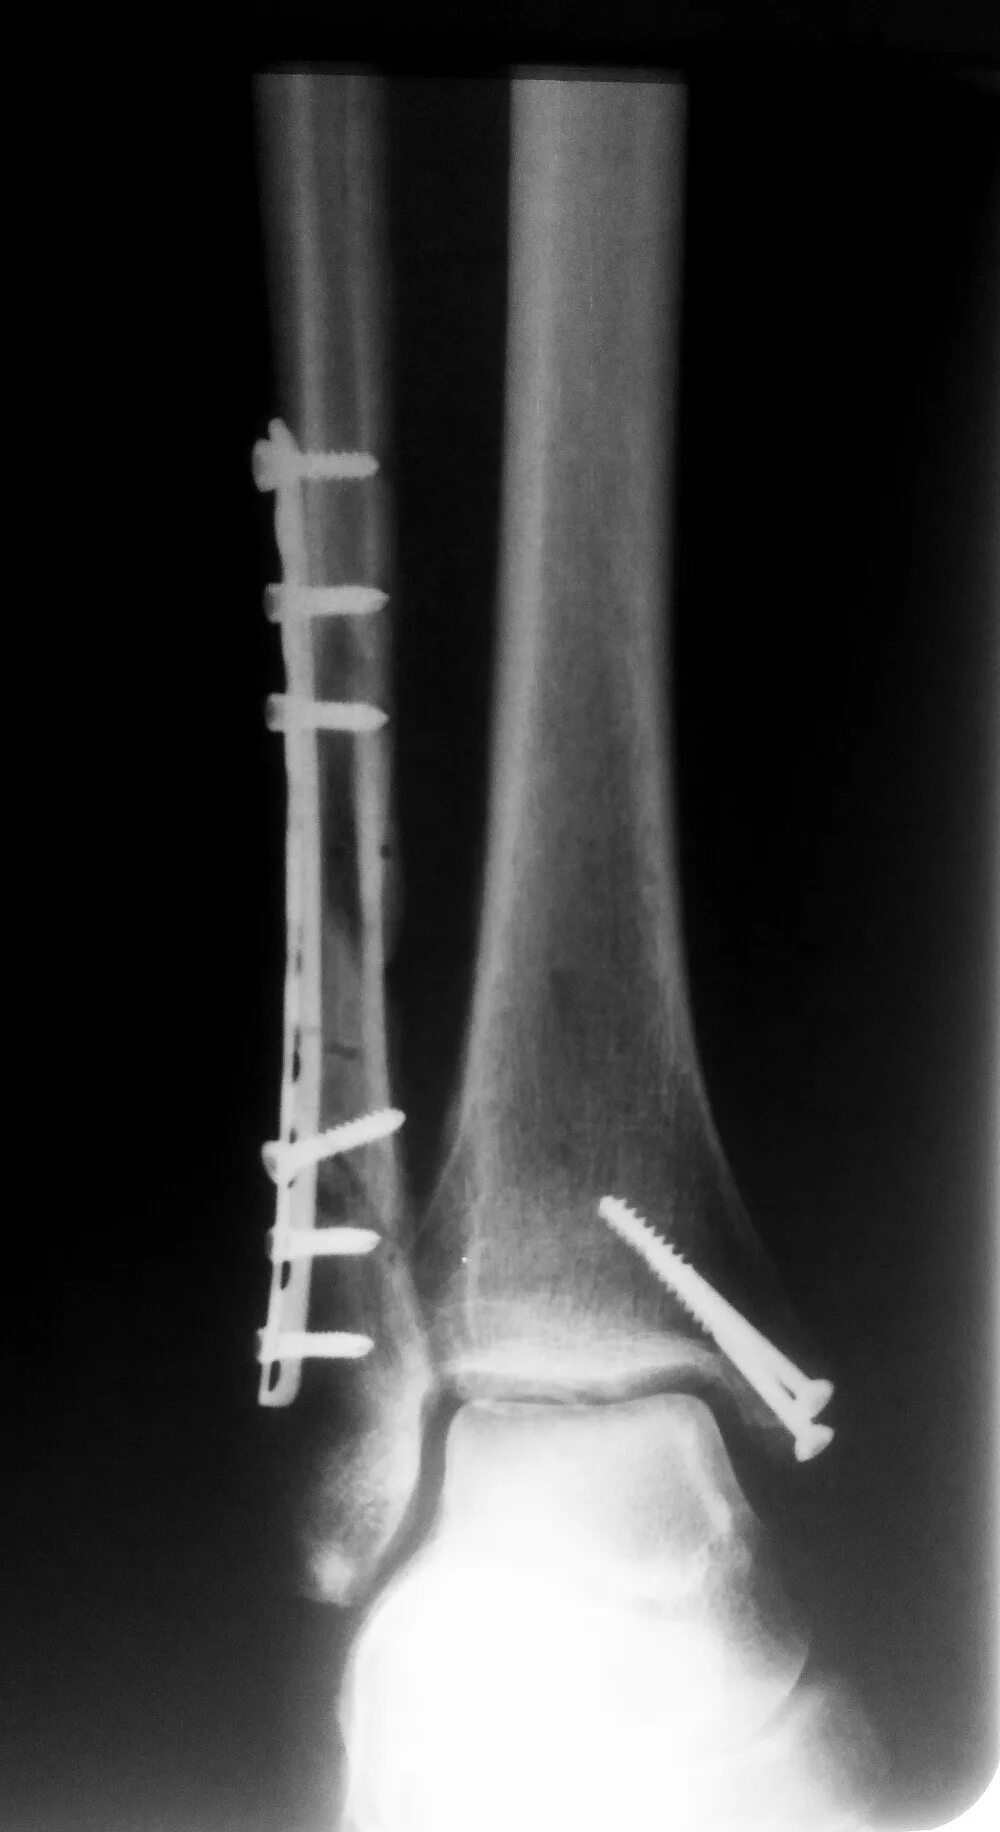

После остеосинтеза лодыжек